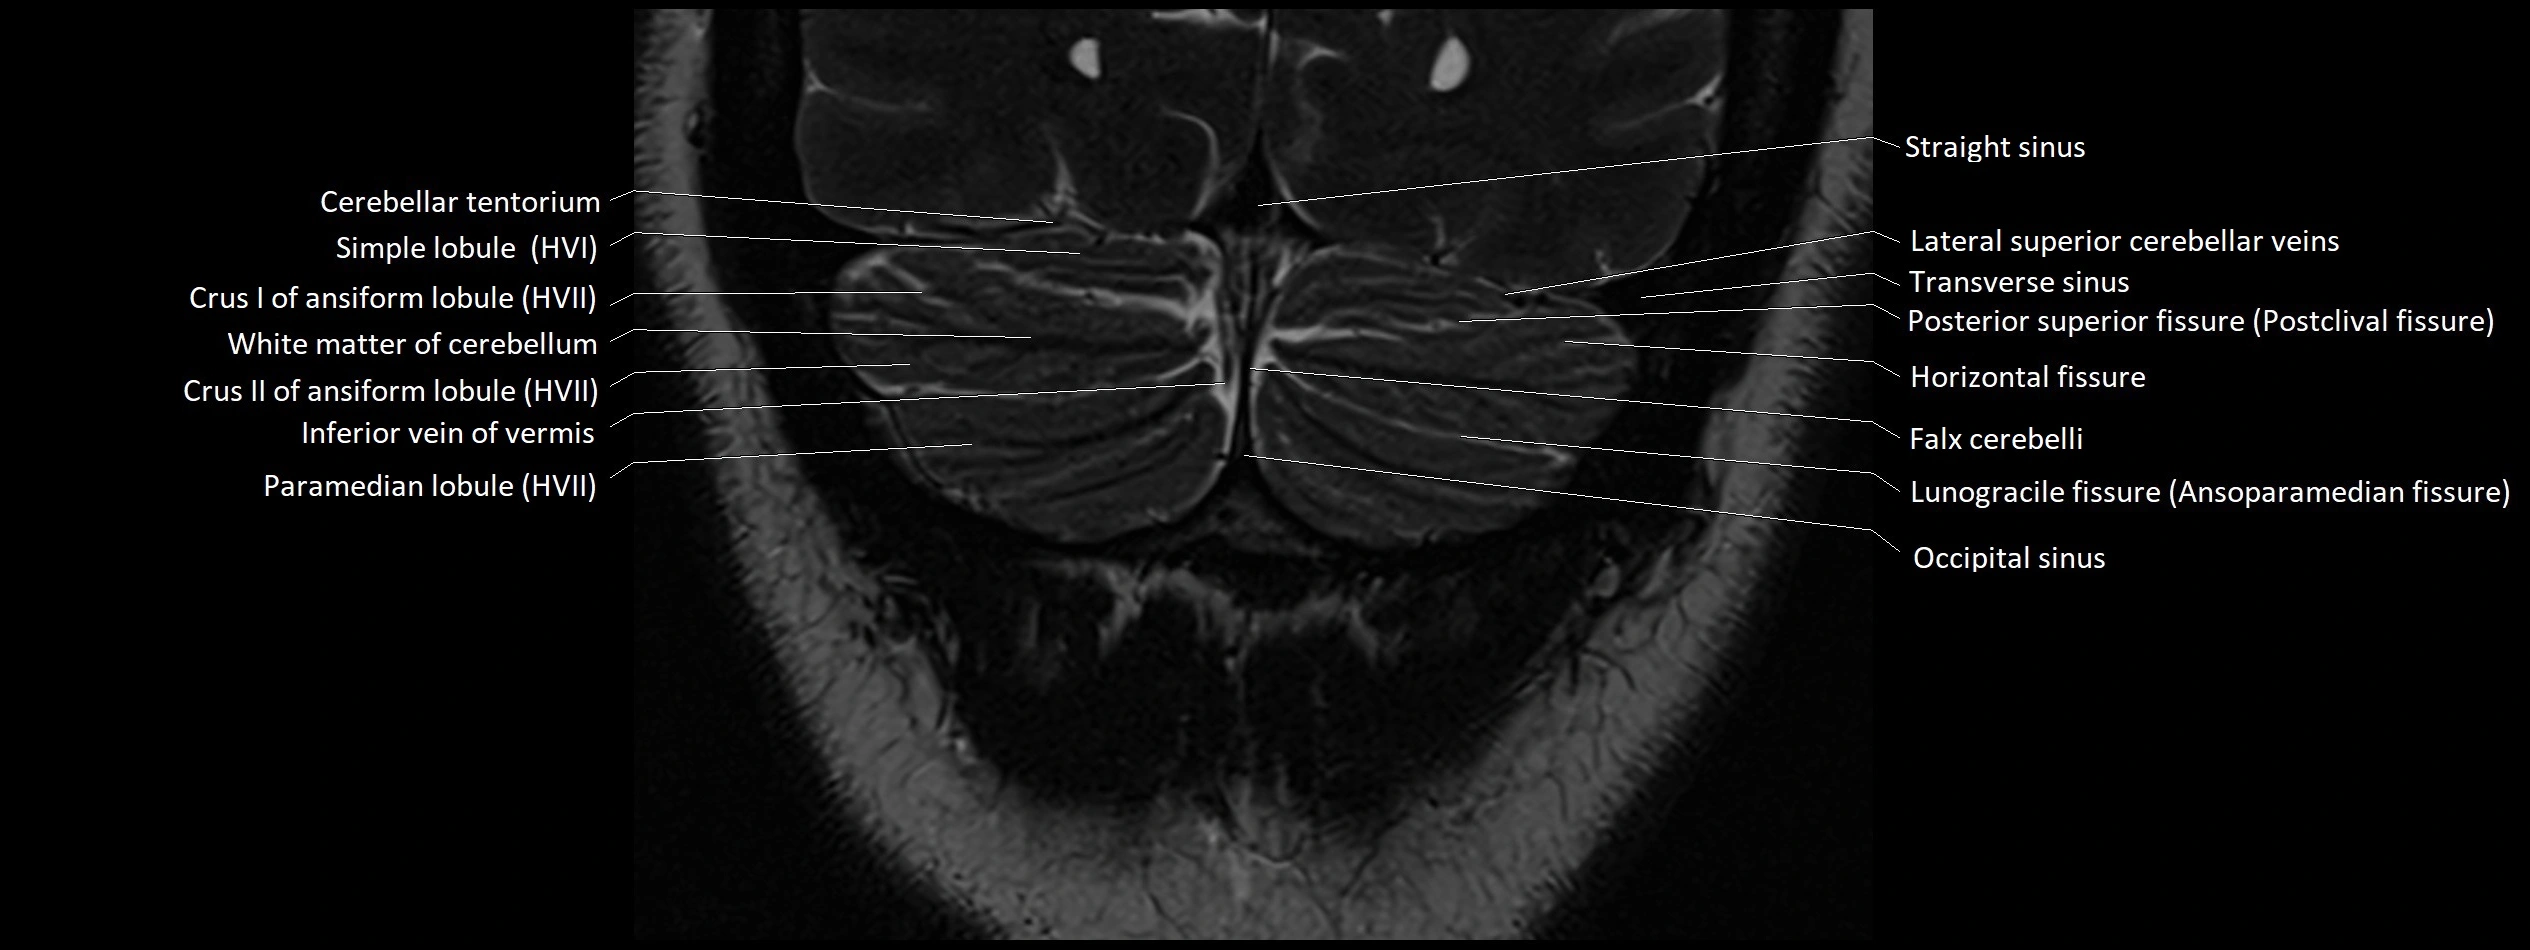

- Horizontal fissure (cerebellum)

- Inferior vein of vermis

- Lunogracle fissure

- Lunogranicile fissure of cerebellum

- Occipital sinus

- Paramedian lobule

- Paramedian lobule (HVII) of cerebellum

- Posterior superior fissure

- Simple lobule

- Simple lobule (HVI) of cerebellum

- Straight sinus

- Superior cerebellar vein

- Superior hemispheric cerebellar veins

- Superior hemispheric veins of the cerebellum

- Transverse sinus

- White matter of cerebellum (Arbor vitae)